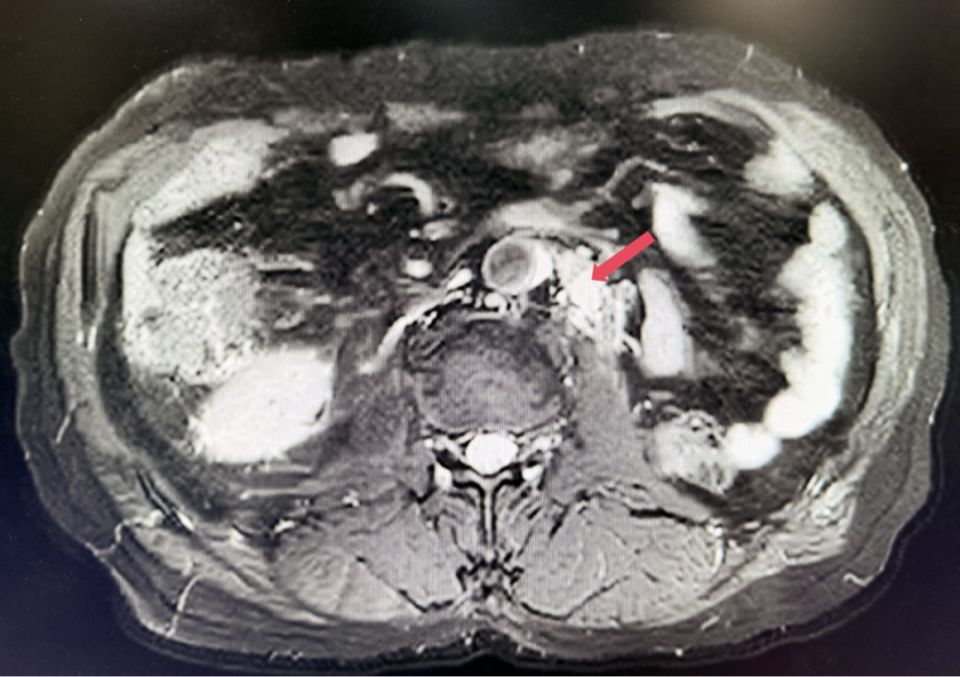

2025年1月:序贯为呋喹替尼单药(5mg,po,qd,D1-14,q3w)治疗。

2026年4月:持续维持PR,PFS超过37个月。

患者初诊时68岁,2020年9月因“体检发现左肾占位2年”行腹腔镜下左肾根治性切除术,术后病理提示为肾透明细胞癌,pT3aN0M0,未行术后辅助治疗、未规律复查。2022年3月胸腹盆CT示腹膜后转移,IMDC评分0分,低危组。随后予一线培唑帕尼治疗,最佳疗效SD,2022年11月PD。于2023年1月经筛选进入Ⅲ期FRUSICA-2临床研究,开始接受呋喹替尼联合信迪利单抗二线治疗,用药6周(C2)后首次肿评即实现疗效PR(缩瘤率40.2%),用药10个月时缩瘤率近七成(68%),并维持上述水平至今,PFS已经超过37个月,在二线治疗中实现了长期无进展生存。同时,患者对呋喹替尼联合信迪利单抗方案耐受性良好,仅见轻微蛋白尿和偶然腹泻,未见其他不良反应,也未见免疫治疗相关不良反应。该方案有望为TKI经治的晚期肾癌患者带来新的选择,为实现长期生存提供可能性。